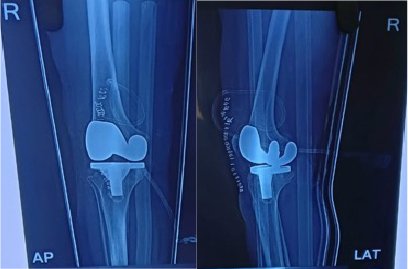

Knee Replacement Surgery, also known as knee arthroplasty, is a surgical procedure that aims to relieve pain and restore function in severely damaged knee joints. It involves replacing the damaged joint surfaces with artificial implants made of metal and plastic.